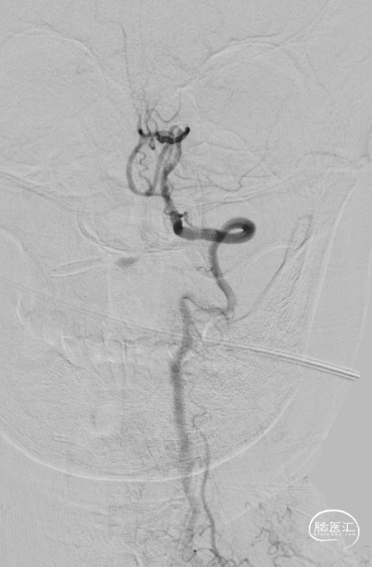

沿微导丝送入3.0mm*16mm Bridge椎动脉雷帕霉素靶向洗脱支架到达目标位置。经手推造影确认定位后,缓慢加压释放支架。

术前行阿司匹林及氯吡格雷双联抗血小板准备。术中拟先行球囊扩张,后行Bridge椎动脉雷帕霉素靶向洗脱支架植入。